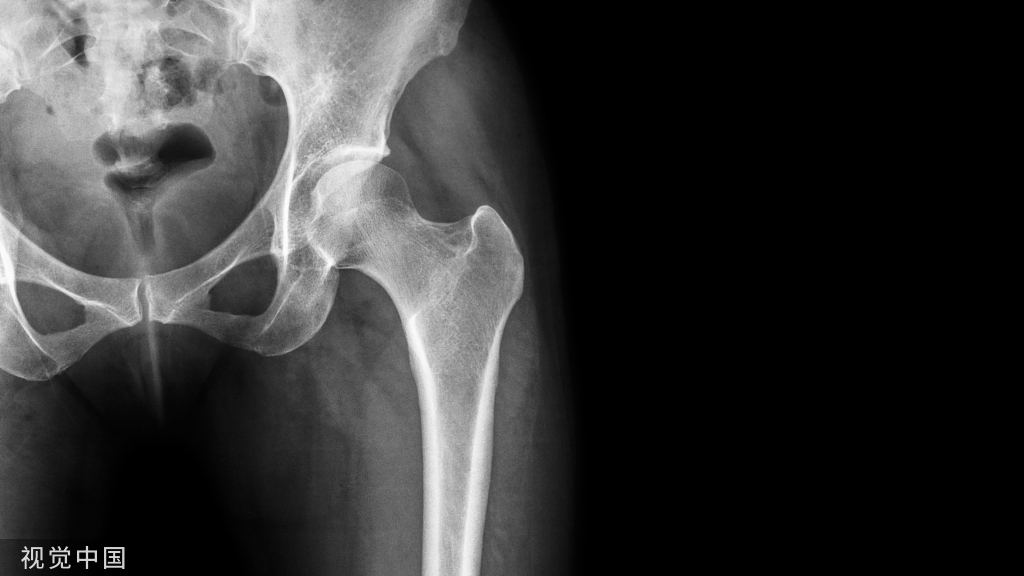

患者31岁,男性,车祸后导致C4-5脱位伴脊髓损伤,行自体髂骨移植融合加钢板内固定术。术后7年出现渐进性吞咽闲难,2个月后出现干咳及发热。颈椎X线片示咽后间隙积气,钡餐检查示巨大袋状食管憩室(图1a),CT显示食管后壁和椎前间隙相通(图1b)。消化道内镜检查发现钢板和螺钉突入食管内。手术取出前路钢板及螺钉,清创后切除憩室,胸骨舌骨肌及肩胛舌骨肌肌瓣修补食管(图1c)。术后留置鼻胃管进行肠内营养10 d后拔除鼻胃管,常规抗生素使用7 d,抑酸。患者于术后2周出院,术后佩戴颈托4周,恢复良好。